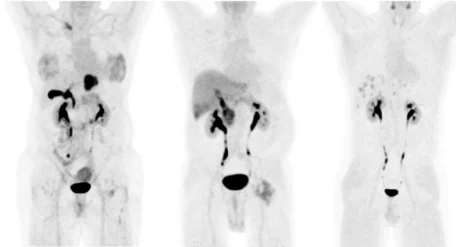

Molecular Imaging Services: PSMA-PET Imaging, FAPI-PET Imaging, and beyond

Perceptive Imaging offers deep expertise in molecular imaging across different types of cancer, with a proven track record in PSMA-PET trials and a growing portfolio of support for emerging radioligand targets. Our team has helped shape the imaging standards for PSMA-based therapies and continues to lead innovation in tracer development, segmentation analytics, and trial design.

We are actively supporting clinical trials in a wide range of novel targets, including FAP, DLL3, HER2, GRPR, MC1R, STEAP1, TROPE2, PTK7, CAIX, and more. Whether you’re working with established tracers or pioneering new theranostic pairs, our imaging infrastructure and scientific leadership will give you confidence in the accuracy, reproducibility, and regulatory-readiness of your data, as you move forward in bringing new treatments, and hope, to the patients who need it the most.

Perceptive is the only imaging core lab to date to support a radioligand therapy FDA submission using AI-derived quantitative PET data. Our proprietary PSMA segmentation platform, updated in April 2025, delivers:

• Fully automated segmentation of both bone and soft tissue lesions

• Dynamic thresholding within patients for improved accuracy across lesion types

• Anatomical labeling of lesions for enhanced interpretability

• Reduced human processing time and improved reproducibility

This tool was developed and validated in the context of the VISION trial, and continues to evolve with new capabilities for emerging tracers and disease states.